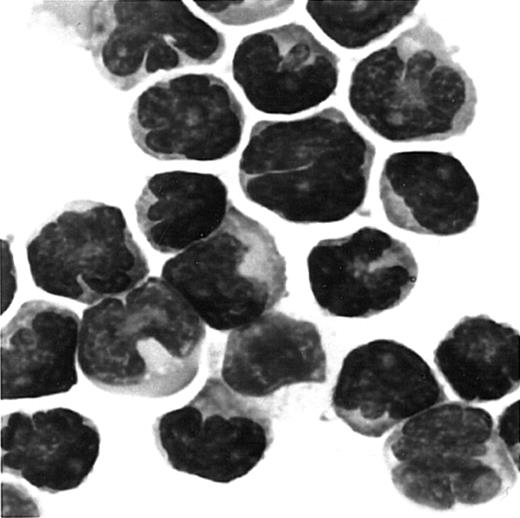

Since ATL cells have characteristic flowerlike nuclei, it is rather easy to identify ATL cells in blood smears. We therefore further carried out immunologic staining of CCR4 using routine blood smears from a total of 7 patients with ATL. Representative results are shown in Figure 4. Again, most ATL cases (6/7) were clearly stained positive for CCR4 (A, B, C: positive; D: negative).

Immunocytologic staining of CCR4 in blood smears.

Routine blood smears obtained from 4 patients with ATL (A-D) were stained for CCR4 as described in “Materials and methods.” Leukemic cells are positive (A, B, C) or negative (D) for CCR4. No staining was seen by an isotype-matched control mouse IgG (not shown).The slides were counterstained by hematoxylin and the original magnification was × 1000.